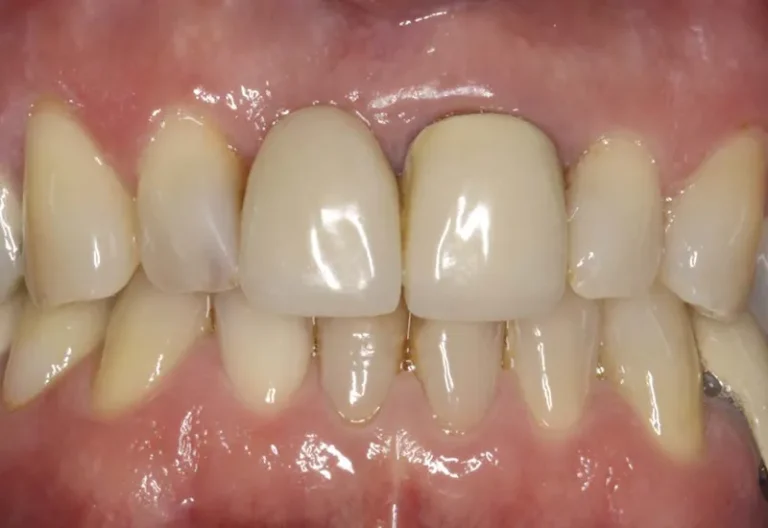

Las diferencias entre implante dental y puente dental son fundamentales para elegir el tratamiento más adecuado. El implante dental consiste en un tornillo de titanio que se inserta en el hueso maxilar, reemplazando la raíz del diente perdido, mientras que el puente dental se apoya en los dientes adyacentes para sostener la prótesis. Aunque ambas…